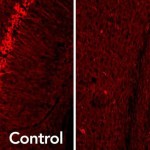

AMD si presenta in forme umida o secca. In entrambe i danni distruggono le cellule nella macula, il piccolo centro della retina nella parte posteriore dell’occhio. E’ compito del macula mettere a fuoco immagini provenienti dall’occhio, che vengono poi convertite in segnali elettrici inviati attraverso il nervo ottico, al cervello. L’infiammazione localizzata nella retina innesca lo sviluppo di drusen, che sono depositi ricchi di lipidi che si accumulano negli occhi come parte naturale del processo di invecchiamento. L’infiammazione e l’ accumulo di drusen distruggerà i fotorecettori nella parte posteriore dell’occhio che ricevono i segnali elettrici dalla retina, causando la perdita della vista.

AMD secca provoca la perdita di cellule nella macula e progredisce più lentamente. La forma umida invece, progredisce rapidamente e provoca una crescita anormale dei vasi sanguigni all’interno della macula.Questi vasi sanguigni alterano la visione a causa della fuoriuscita di liquido negli occhi e sono il risultato di incontrollata vascular endothelial growth factor (VEGF) che stimola lo sviluppo di nuovi vasi sanguigni.